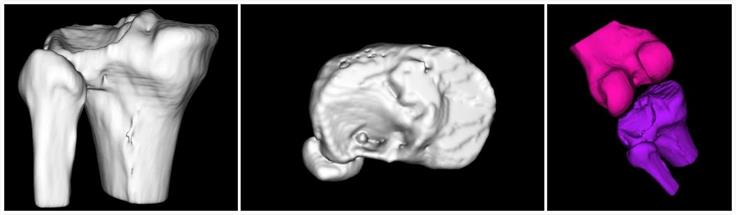

- 模擬病人骨折,讓醫(yī)生更直觀的了解骨折情況

- 軟件模擬手術(shù)入路,為醫(yī)生選擇最佳入路提供參考

該手術(shù)在軟件的輔助下確定以不剔除腓骨的方式進(jìn)行手術(shù)